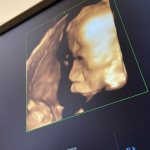

Я сходила сегодня, мне что-то кажется не то с губами) или это пройдёт?

Узист сказала что всё в норме, отекает типа от окоплодных вод)